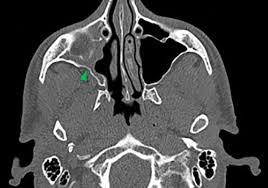

The visual sign of silent sinus syndrome is the asymmetry of the face and the asymmetry of face may lead to many other problems like diplopia. Recent findings Silent sinus syndrome lies on a spectrum of other forms of sinus-related orbitopathy. Radiographic features of disease include an opacified and hypoplastic sinus a lateralized uncinate process depression of the orbital.

The first case of maxillary sinus opacification and atelectasis was reported by Montgomery in 1964 It was not until 30 years later however that the term silent sinus syndrome was attributed to this phenomenon Patients typically present with unilateral painless enophthalmos and hypoglobus progressing over a period of several months. The silent sinus syndrome is characterized by painless enophthalmos associated with involution of the maxillary sinus after infundibular occlusion 12345678910. The hypoventilation over time results in resorption of.

Figure 6 From Bilateral Silent Sinus Syndrome Case Report And Surgical Solution Semantic Scholar

Silent sinus syndrome is rare and multiple findings are needed for the diagnosis. The hypoventilation over time results in resorption of. Diplopia is seen in about 28 to 65 of cases regarding silent sinus syndrome. Silent sinus syndrome is more common in patients in their 30s and 40s ranging from 19 to 82 years mean 39 without gender or laterality bias. These include enophthalmos or hypoglobus in the absence of clinically evident sinonasal inflammatory disease. The first case of maxillary sinus opacification and atelectasis was reported by Montgomery in 1964 It was not until 30 years later however that the term silent sinus syndrome was attributed to this phenomenon Patients typically present with unilateral painless enophthalmos and hypoglobus progressing over a period of several months. 5 The proposed mechanism for the development of silent sinus syndrome is a hypoventilated maxillary sinus from an obstructed ostiomeatal complex. The silent sinus syndrome is a spontaneous unilateral maxillary atelectasis with complete or partial opacification of the sinus. The silent sinus syndrome is a rare clinical entity of spontaneous enophthalmos and hypoglobus caused by an alteration of the normal orbital architecture and function from maxillary sinus collapse in the setting of chronic sinusitis.

When looking at all the pictures on google the symptoms its all matching. Ocular motility limitation also occur and sometimes reported along with hypo Globus. Silent sinus syndrome is more common in patients in their 30s and 40s ranging from 19 to 82 years mean 39 without gender or laterality bias. Silent sinus syndrome is usually diagnosed in patients in their 30s and 40s with a mean age of 39 and a range of 19 to 82 11. Radiographic features of disease include an opacified and hypoplastic sinus a lateralized uncinate process depression of the orbital. Uncommon presentations and descriptions of sinus involvement other than the maxillary sinus add to the variability of presentation. These include enophthalmos or hypoglobus in the absence of clinically evident sinonasal inflammatory disease.